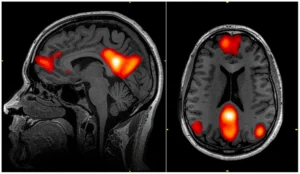

Default Mode Network mindfulness . Discover how quieting your Default Mode Network can free you from obsessive thinking, restore presence, and unlock the peace that exists beneath constant mental noise.

Mindfulness neuroscience. Discover how what contemplatives have known for millennia is now verified by neuroscience—and why your brain’s transformation through daily practice might be the most important thing you learn this year.